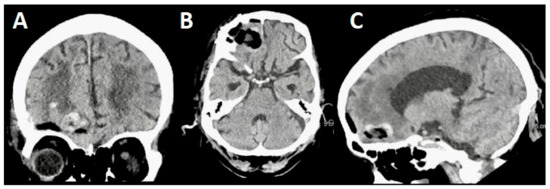

3.1. Case 1

3.1.1. Demography, Presentation, and Evaluation

3.1.2. Intervention

3.1.3. Postoperative Period